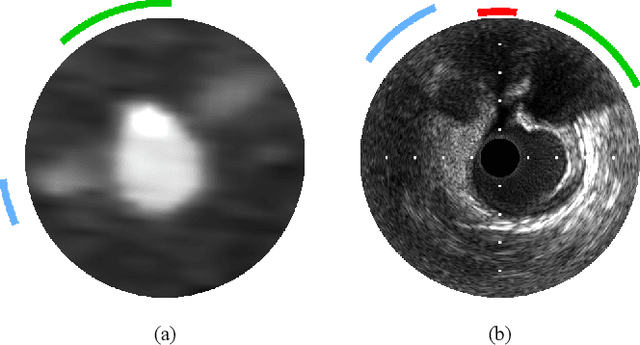

Coronary CT angiography (CCTA) and intravascular ultrasound (IVUS) provide complementary information for coronary artery disease assessment, making their registration valuable for comprehensive analysis. However, existing registration methods require manual interaction or extensive segmentations, limiting their practical application. In this work, we present a fully automatic framework for CCTA-IVUS registration using deep learning-based feature detection and a differentiable image registration module. Our approach leverages a convolutional neural network trained to identify key anatomical features from polar-transformed multiplanar reformatted CCTA or IVUS data. These detected anatomical featuers subsequently guide a differentiable registration module to optimize transformation parameters of an automatically extracted coronary artery centerline. The method does not require landmark selection or segmentations as input, while accounting for the presence of IVUS guidewire artifacts. Evaluated on 48 clinical cases with reference CCTA centerlines corresponding to IVUS pullback, our method achieved successful registration in 83.3\% of cases, with a median centerline overlap F$_1$-score of 0.982 and median cosine similarities of 0.940 and 0.944 for cross-sectional plane orientation. Our results demonstrate that automatically detected anatomical features can be leveraged for accurate registration. The fully automatic nature of the approach represents a significant step toward streamlined multimodal coronary analysis, potentially facilitating large-scale studies of coronary plaque characteristics across modalities.